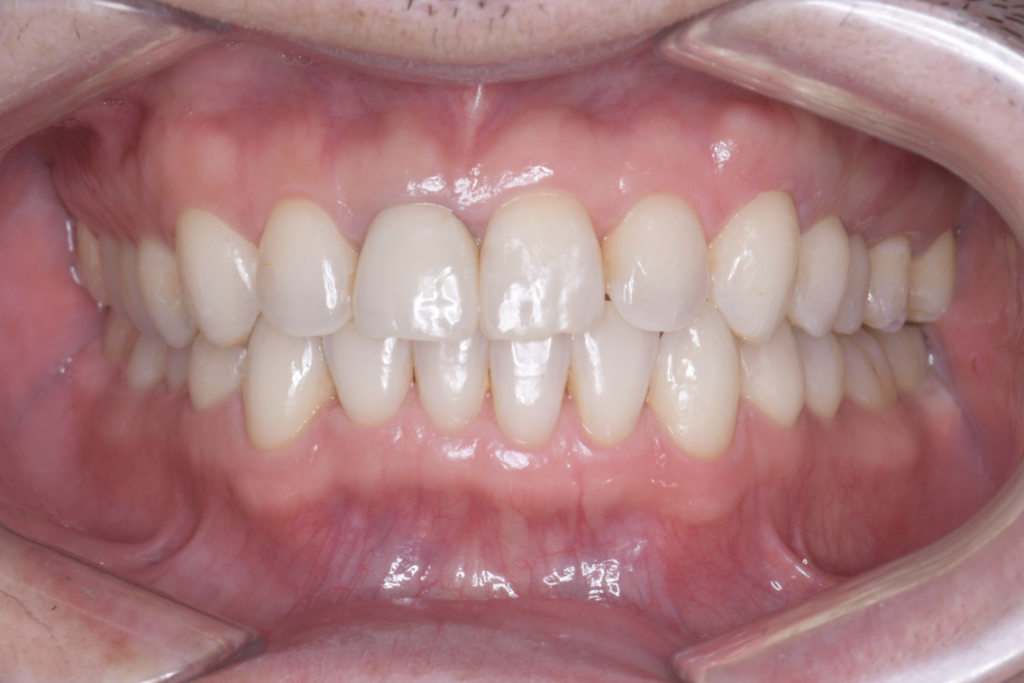

以下の症例写真例は、40代男性の症例です。

前歯のがたつきを改善するためにインビザラインによる矯正とセラミックインレー、根管治療を行い、金属を使わないメタルフリー治療を実施しました。

見た目と機能の両面で大きく改善している様子がわかります。

<術後の症例写真>